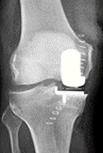

Til venstre ses en delprotese. Til højre ses delprotesen indsat i knæ.

Knæledsprotesen består af 3 dele

- Protesedelen på lårbenet er af rustfrit stål.

- Protesedelen på skinnebenet er af rustfrit stål eller titanium og består af en metalplade med køl, som går ned i marvhulen på skinnebenet. Oven på metalpladen sidder en del af hård plastik, som danner led med protesedelen på lårbenet.

- Protesedelen på knæskallen er af plastik.

Protesedelen kan enten gøres fast til knoglerne med knoglecement, der binder som lim eller uden knoglecement, hvor protesen har en overflade, som knoglen vokser ind i.

Den knoglecement, vi anvender, er af et fabrikat, som har været anvendt i mere end 30 år uden problemer.